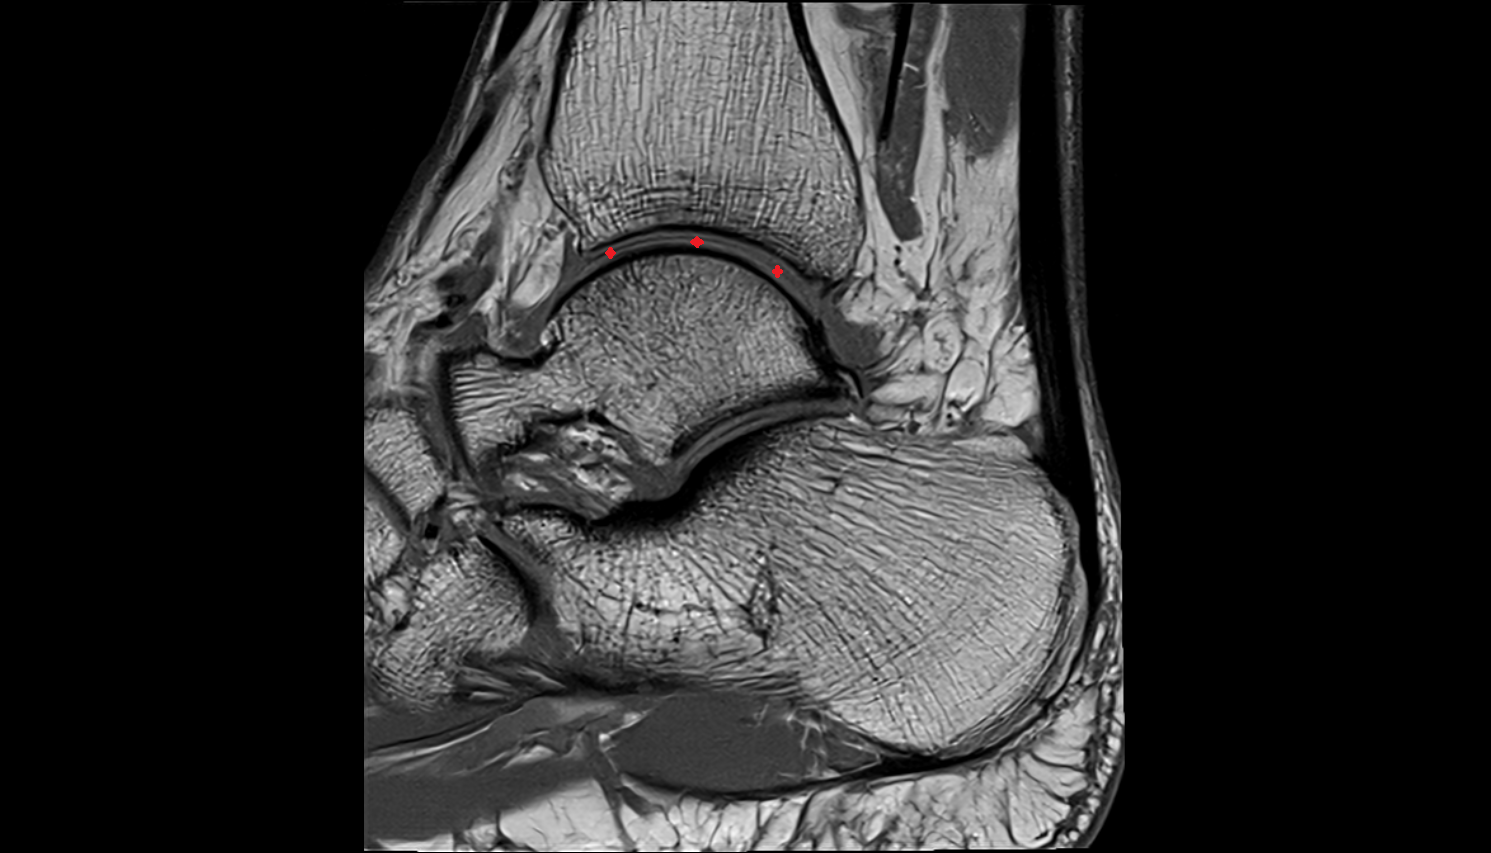

- Talus

- Body of talus

- Calcaneus

- Sustentaculum tali

- Ankle joint

- Talocalcaneal joint

- Achilles tendon